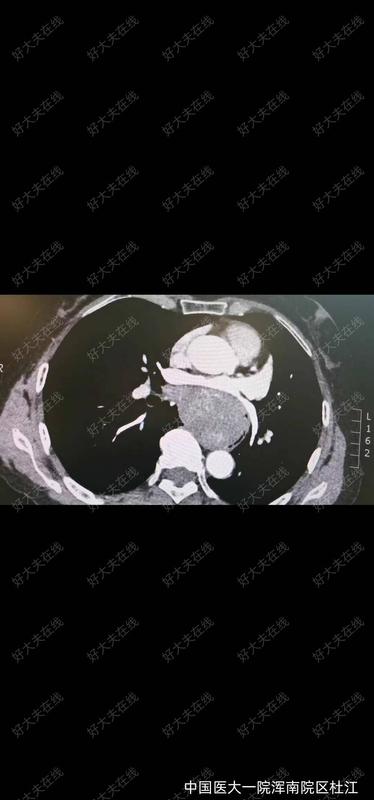

越来越多的健康人群开始重视胃肠镜体检,有些人拿到报告后,在胃镜检查报告中,发现有胃“SMT”的字样,很紧张,甚至以为自己得了什么绝症。今天,我们就简单来介绍一下胃SMT。SMT意思是消化道黏膜下肿瘤(SubMucosalTumor,SMT)。这是指一类来自消化道黏膜以下组织的肿块,包括起源于黏膜肌层、黏膜下层和固有肌层的肿瘤。它们在内镜下的表现形态相似,即表面覆有正常黏膜的隆起性病变,医生一般不取活检,因为活检取不到黏膜下的组织。发现SMT后,可能会被要求做个超声内镜(EndoscopicUltrasonography,EUS),有的时候会联合消化道增强CT,以确定肿瘤的来源层次、大小、质地及与周边组织血管的毗邻关系。上消化道的SMT以食管和胃最为常见,十二指肠较少见。最常见的上消化道SMT包括平滑肌瘤、间质瘤、神经内分泌肿瘤、脂肪瘤、颗粒细胞瘤、神经鞘瘤等。非肿瘤性病变的异位胰腺也会表现为SMT样。 胃黏膜下肿瘤发病率约十万分之一。患者很少有症状,大部分是因为体检胃镜无意中发现。如果肿瘤持续长大,影响食物通过或者表面有糜烂破溃时,则会出现疼痛、消化道出血等不适。那么发现了胃黏膜下肿瘤,到底是否需要切除呢,一般来说小于1cm的SMT,建议随访。当出现以下这些情况时,建议切除: 1)有症状(伴有出血、消化道梗阻等); 2)无症状但不断增大的黏膜下肿瘤; 3)明确是胃间质瘤(有恶性潜能,随直径增大恶性潜能增大); 4) 肿瘤大于2cm怀疑是胃间质瘤; 5) 性质不明确的黏膜下肿瘤,但是不能耐受或者因为焦虑不愿长期内镜检查随访。胃镜下手术创伤小,恢复快,是较小的黏膜下肿瘤治疗的优选(一般来说小于5cm的间质瘤,像平滑肌瘤更大也可以内镜下切除),可以完整切除后病理检查明确肿瘤性质内镜下的手术方式包括内镜黏膜下剥离术(ESD)、内镜黏膜下挖除术(ESE)、内镜全层切除术(EFTR)和内镜经黏膜下隧道肿瘤切除术(STER)。胃镜发现的SMT是胃癌吗?如何治疗?段本松 东方内镜 2024年07月27日17:40 上海 12人胃镜发现的SMT是胃癌吗?如何治疗?徐美东消化内镜工匠创新工作室科普系列文章越来越多的健康人群开始重视胃肠镜体检,有些人拿到报告后,在胃镜检查报告中,发现有胃“SMT”的字样,很紧张,甚至以为自己得了什么绝症。今天,我们就简单来介绍一下胃SMT。SMT意思是消化道黏膜下肿瘤(SubMucosalTumor,SMT)。这是指一类来自消化道黏膜以下组织的肿块,包括起源于黏膜肌层、黏膜下层和固有肌层的肿瘤。它们在内镜下的表现形态相似,即表面覆有正常黏膜的隆起性病变,医生一般不取活检,因为活检取不到黏膜下的组织。发现SMT后,可能会被要求做个超声内镜(EndoscopicUltrasonography,EUS),有的时候会联合消化道增强CT,以确定肿瘤的来源层次、大小、质地及与周边组织血管的毗邻关系。上消化道的SMT以食管和胃最为常见,十二指肠较少见。最常见的上消化道SMT包括平滑肌瘤、间质瘤、神经内分泌肿瘤、脂肪瘤、颗粒细胞瘤、神经鞘瘤等。非肿瘤性病变的异位胰腺也会表现为SMT样。 胃黏膜下肿瘤发病率约十万分之一。患者很少有症状,大部分是因为体检胃镜无意中发现。如果肿瘤持续长大,影响食物通过或者表面有糜烂破溃时,则会出现疼痛、消化道出血等不适。那么发现了胃黏膜下肿瘤,到底是否需要切除呢,一般来说小于1cm的SMT,建议随访。当出现以下这些情况时,建议切除: 1)有症状(伴有出血、消化道梗阻等); 2)无症状但不断增大的黏膜下肿瘤; 3)明确是胃间质瘤(有恶性潜能,随直径增大恶性潜能增大); 4) 肿瘤大于2cm怀疑是胃间质瘤; 5) 性质不明确的黏膜下肿瘤,但是不能耐受或者因为焦虑不愿长期内镜检查随访。胃镜下手术创伤小,恢复快,是较小的黏膜下肿瘤治疗的优选(一般来说小于5cm的间质瘤,像平滑肌瘤更大也可以内镜下切除),可以完整切除后病理检查明确肿瘤性质内镜下的手术方式包括内镜黏膜下剥离术(ESD)、内镜黏膜下挖除术(ESE)、内镜全层切除术(EFTR)和内镜经黏膜下隧道肿瘤切除术(STER)。接下来,我将结合我中心的实际临床病例,为大家介绍最常见的两种胃镜下发现的SMT:平滑肌瘤、间质瘤。01食管胃平滑肌瘤平滑肌瘤(Leiomyoma)是一种良性间叶肿瘤,具有平滑肌分化特征。胃镜发现的平滑肌瘤主要分布在食管和胃,尤其以食管为主,常见于食管胃交界处和食管中部。大多数患者无症状,当肿瘤增大时可能出现吞咽困难、疼痛或不适,常见的主诉包括胸骨后、剑突下或上腹部的疼痛或不适,以及上腹部饱胀感或压迫感。其他消化道非特异性症状包括食欲不振、反胃、嗳气、恶心和呕吐等。目前,内镜下对平滑肌瘤的诊断及处理已经非常成熟。病例1:食管平滑肌瘤患者女,37岁,外院胃镜检查发现食管距门齿35cm-37cm处有一黏膜下隆起,遂来我院行超声内镜检查。检查提示隆起处有均匀低回声团块,边界清晰,回声与固有肌层连续,截面大小约2.02.0cm,结合CT报告考虑平滑肌瘤可能。我中心决定采用内镜经黏膜下隧道肿瘤切除术(STER)进行肿瘤切除,手术顺利取出大小约2.5cm的平滑肌瘤。病例2:胃近贲门平滑肌瘤患者女,55岁,1年前当地医院胃镜检查发现胃底黏膜下隆起,未予重视,未服药及规范随访。近日复查内镜发现胃底黏膜下隆起较之前增大,遂来我院诊治。CT提示贲门占位,大小约4.0cm。结合超声胃镜结果,考虑贲门SMT,平滑肌瘤可能。我中心决定采用STER进行肿瘤切除,手术顺利,取出大小约4.0cm的马蹄样平滑肌瘤。胃镜发现的SMT是胃癌吗?如何治疗?段本松 东方内镜 2024年07月27日17:40 上海 12人胃镜发现的SMT是胃癌吗?如何治疗?徐美东消化内镜工匠创新工作室科普系列文章越来越多的健康人群开始重视胃肠镜体检,有些人拿到报告后,在胃镜检查报告中,发现有胃“SMT”的字样,很紧张,甚至以为自己得了什么绝症。今天,我们就简单来介绍一下胃SMT。SMT意思是消化道黏膜下肿瘤(SubMucosalTumor,SMT)。这是指一类来自消化道黏膜以下组织的肿块,包括起源于黏膜肌层、黏膜下层和固有肌层的肿瘤。它们在内镜下的表现形态相似,即表面覆有正常黏膜的隆起性病变,医生一般不取活检,因为活检取不到黏膜下的组织。发现SMT后,可能会被要求做个超声内镜(EndoscopicUltrasonography,EUS),有的时候会联合消化道增强CT,以确定肿瘤的来源层次、大小、质地及与周边组织血管的毗邻关系。上消化道的SMT以食管和胃最为常见,十二指肠较少见。最常见的上消化道SMT包括平滑肌瘤、间质瘤、神经内分泌肿瘤、脂肪瘤、颗粒细胞瘤、神经鞘瘤等。非肿瘤性病变的异位胰腺也会表现为SMT样。 胃黏膜下肿瘤发病率约十万分之一。患者很少有症状,大部分是因为体检胃镜无意中发现。如果肿瘤持续长大,影响食物通过或者表面有糜烂破溃时,则会出现疼痛、消化道出血等不适。那么发现了胃黏膜下肿瘤,到底是否需要切除呢,一般来说小于1cm的SMT,建议随访。当出现以下这些情况时,建议切除: 1)有症状(伴有出血、消化道梗阻等); 2)无症状但不断增大的黏膜下肿瘤; 3)明确是胃间质瘤(有恶性潜能,随直径增大恶性潜能增大); 4) 肿瘤大于2cm怀疑是胃间质瘤; 5) 性质不明确的黏膜下肿瘤,但是不能耐受或者因为焦虑不愿长期内镜检查随访。胃镜下手术创伤小,恢复快,是较小的黏膜下肿瘤治疗的优选(一般来说小于5cm的间质瘤,像平滑肌瘤更大也可以内镜下切除),可以完整切除后病理检查明确肿瘤性质内镜下的手术方式包括内镜黏膜下剥离术(ESD)、内镜黏膜下挖除术(ESE)、内镜全层切除术(EFTR)和内镜经黏膜下隧道肿瘤切除术(STER)。接下来,我将结合我中心的实际临床病例,为大家介绍最常见的两种胃镜下发现的SMT:平滑肌瘤、间质瘤。01食管胃平滑肌瘤平滑肌瘤(Leiomyoma)是一种良性间叶肿瘤,具有平滑肌分化特征。胃镜发现的平滑肌瘤主要分布在食管和胃,尤其以食管为主,常见于食管胃交界处和食管中部。大多数患者无症状,当肿瘤增大时可能出现吞咽困难、疼痛或不适,常见的主诉包括胸骨后、剑突下或上腹部的疼痛或不适,以及上腹部饱胀感或压迫感。其他消化道非特异性症状包括食欲不振、反胃、嗳气、恶心和呕吐等。目前,内镜下对平滑肌瘤的诊断及处理已经非常成熟。病例1:食管平滑肌瘤患者女,37岁,外院胃镜检查发现食管距门齿35cm-37cm处有一黏膜下隆起,遂来我院行超声内镜检查。检查提示隆起处有均匀低回声团块,边界清晰,回声与固有肌层连续,截面大小约2.02.0cm,结合CT报告考虑平滑肌瘤可能(图1)。我中心决定采用内镜经黏膜下隧道肿瘤切除术(STER)进行肿瘤切除,手术顺利取出大小约2.5cm的平滑肌瘤(图2)。病例2:胃近贲门平滑肌瘤患者女,55岁,1年前当地医院胃镜检查发现胃底黏膜下隆起,未予重视,未服药及规范随访。近日复查内镜发现胃底黏膜下隆起较之前增大,遂来我院诊治。CT提示贲门占位,大小约4.0cm。结合超声胃镜结果,考虑贲门SMT,平滑肌瘤可能(图3)。我中心决定采用STER进行肿瘤切除,手术顺利,取出大小约4.0cm的马蹄样平滑肌瘤(图4)。02胃肠道间质瘤胃肠道间质瘤(GIST)是消化道最常见的间叶源性肿瘤,约占全消化道肿瘤的3%。在消化道中,以胃最为常见,其他部位较少见。因此,胃镜下发现的间质瘤大多位于胃部。该肿瘤可发生于任何年龄。男女发病差异不明显。早期多无症状,由于其球状非侵袭性的生长方式,即便肿瘤较大也不一定产生压迫感和出血,是一种很难在早期发现的隐形杀手。随着内镜检查的普及和技术进步,早期发现和超级微创治疗GIST已经成为可能。内镜下的超级微创手术治疗GIST不仅创伤小、痛苦少、操作时间短、并发症少,还能提供完整的病理学诊断资料,以便制定预后和随访策略。病例3:胃底间质瘤患者女,76岁,半年前体检时胸部CT平扫提示胃底可疑占位。病程中,患者偶有反酸,无其他不适。再次复查胸部CT提示胃底可疑占位,超声胃镜显示病灶呈均匀低回声,边界清楚,起源于固有肌层,大小约26mm24mm,结合CT报告考虑间质瘤伴钙化可能。我中心决定采用内镜全层切除术(EFTR)进行肿瘤切除,手术顺利取出大小约3.5cm的间质瘤。总之,胃镜检查发现胃SMT后,无需过分紧张,需要寻求专业的内镜医生意见,随访或内镜下切除,如果较大无法内镜下切除则需要考虑外科手术治疗。